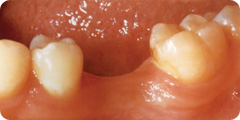

Problem: fehlender Molar im Unterkiefer

|